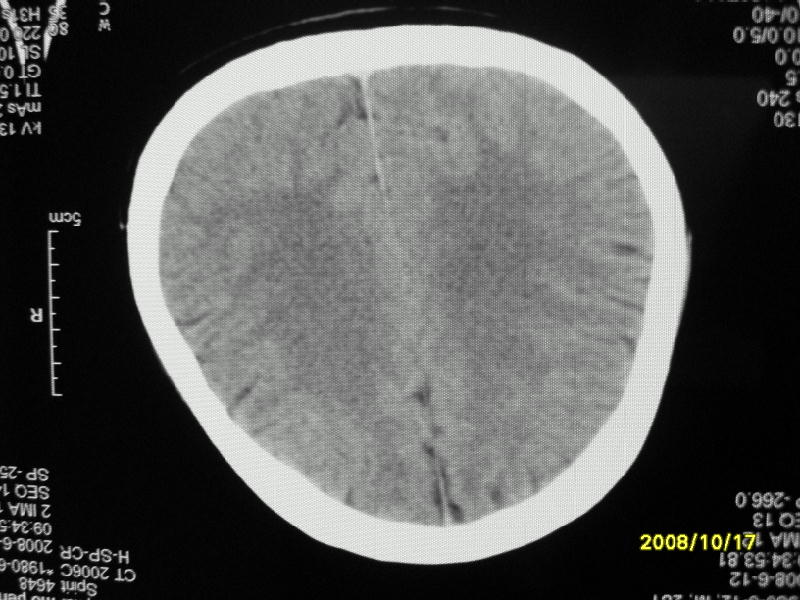

检查名称:     ct颅脑平扫           男     28岁

表现:左顶叶见斑点状致密影。边缘清,大小约0。3*1。0cm,余脑实质密度及灰白质结构示见异常。脑室系统大小,形态,密度未见异常。脑沟。脑裂。脑池未见异常密度影。中线结构无移位。

印象:左顶叶少许钙化灶

左顶叶见斑点状致密影。边缘清,大小约0。3*1。0cm,余脑实质密度及灰白质结构示见异常。脑室系统大小,形态,密度未见异常。脑沟。脑裂。脑池未见异常密度影。中线结构无移位。

印象:左顶叶少许钙化灶。

镰旁钙化

镰旁钙化或顶骨内板骨嵴部分容积效应,建议mri矢状位扫描观察与顶骨的关系。排外后者。

左顶叶见斑点状致密影